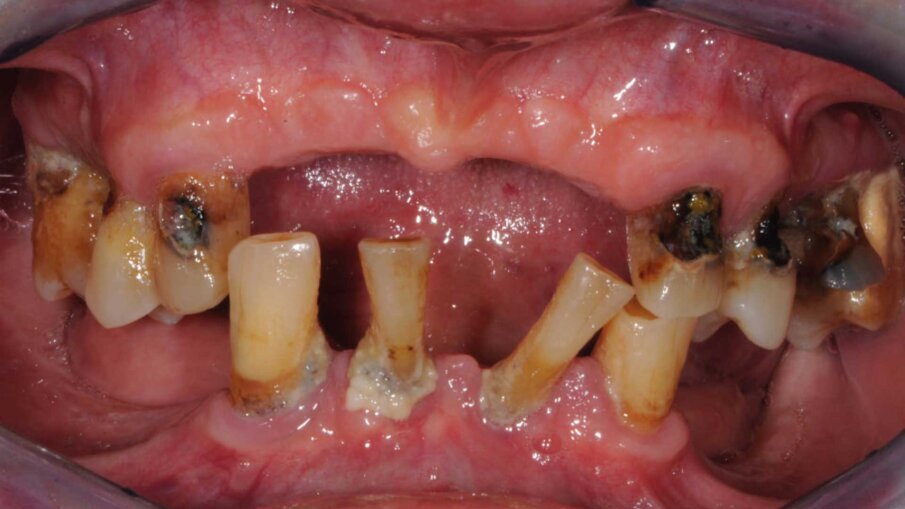

Il paziente si presentò alla nostra osservazione lamentando una diminuzione della capacità masticatoria. All’osservazione clinica e radiografica (Figg. 1, 2) si evidenziava la mancanza di numerosi elementi dentari e di una diffusa malattia parodontale, il tutto complicato dalla presenza di carie destruenti su tutti gli elementi dentari con migrazione degli stessi. Lo spostamento dei denti aveva portato a perdita della dimensione verticale e di tutti i punti di riferimento per la ricostruzione della dentatura.